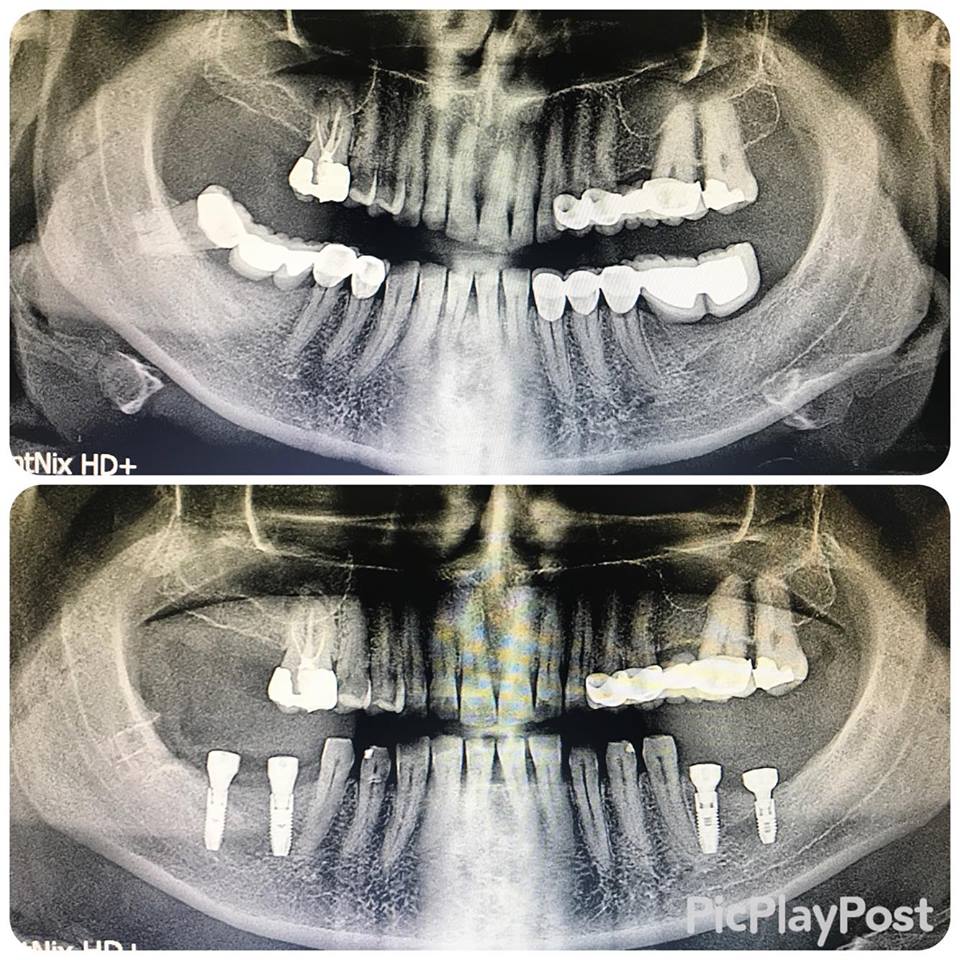

İMPLANT TEDAVİSİ

implant tedavisi